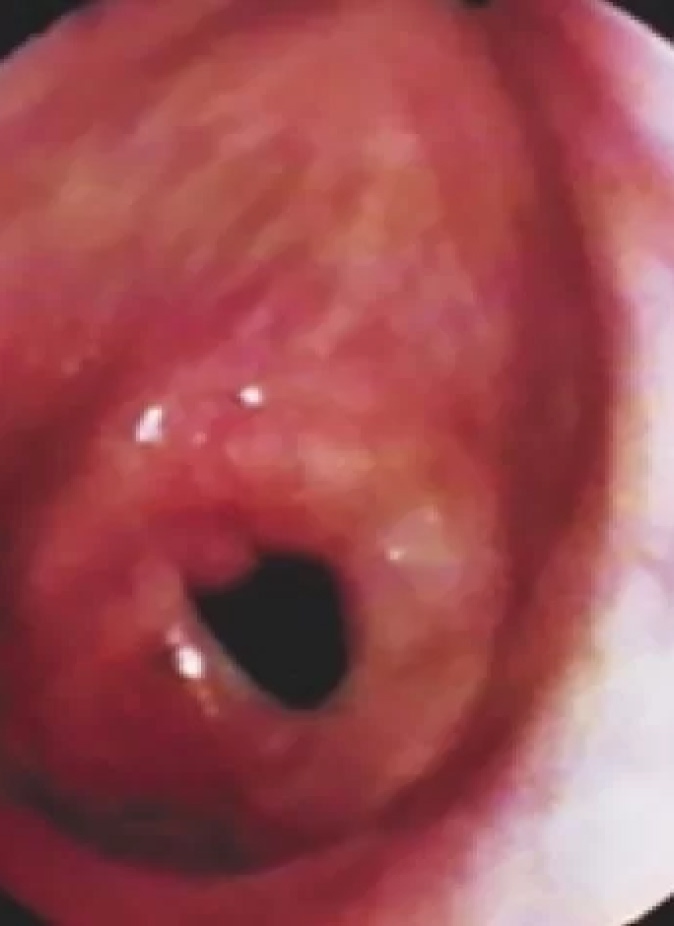

La estenosis subglótica y traqueal son dos términos diferentes que se utilizan para describir un estrechamiento en las vías respiratorias superiores (tráquea o tráquea) o en el área justo debajo de las cuerdas vocales. Esta condición puede ser congénita o adquirida.

Hay muchas causas de estenosis subglótica y estenosis traqueal, pero todas tienen su origen en una lesión en la tráquea que resulta en una cicatriz redonda, que finalmente estrecha el espacio para respirar. La estenosis subglótica adquirida es causada más comúnmente por intubación prolongada.

Si la lesión está justo debajo de las cuerdas vocales, puede interferir con el funcionamiento de las cuerdas vocales y provocar cambios en la voz. Una lesión que está un poco más abajo en la tráquea puede causar dificultad para respirar ya que la cicatriz (estenosis) estrecha las vías respiratorias. Los síntomas adicionales pueden incluir respiración ruidosa (estridor inspiratorio / espiratorio) y tos.